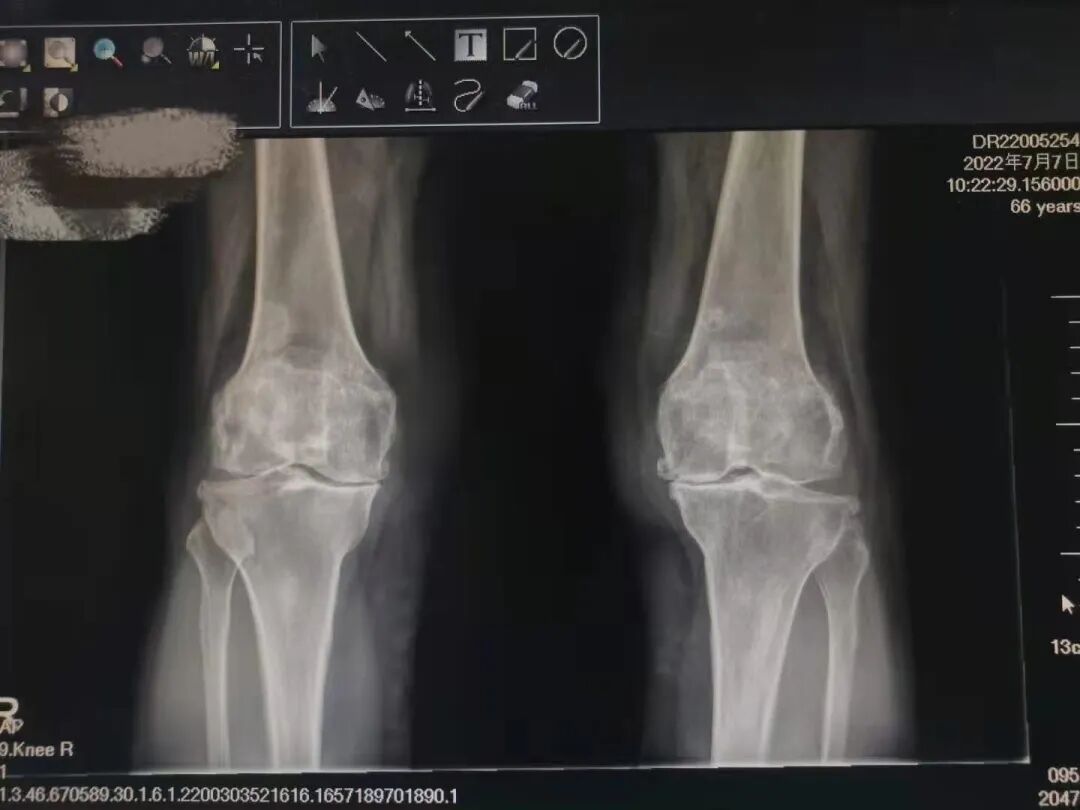

術(shù)前雙下肢X線片